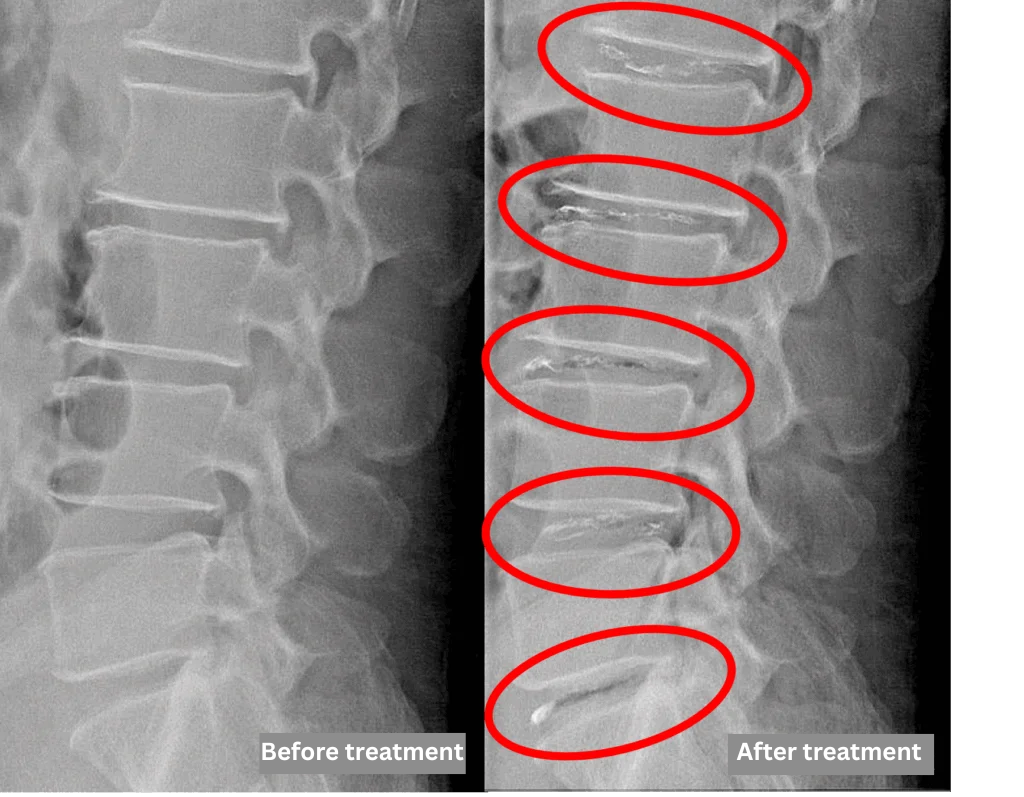

- L1/2, L2/3, L3/4, L4/5, and L5/S – Disc degeneration and lumbar disc herniation

The above findings were also observed on the imaging.

The disc findings from L1/2 through L5/S were observed to be compressing the spinal canal and are the most likely cause of the patient’s symptoms.

After consulting with the patient, the Cellgel Method was performed on L1/2, 2/3, 3/4, 4/5 and 5/s.